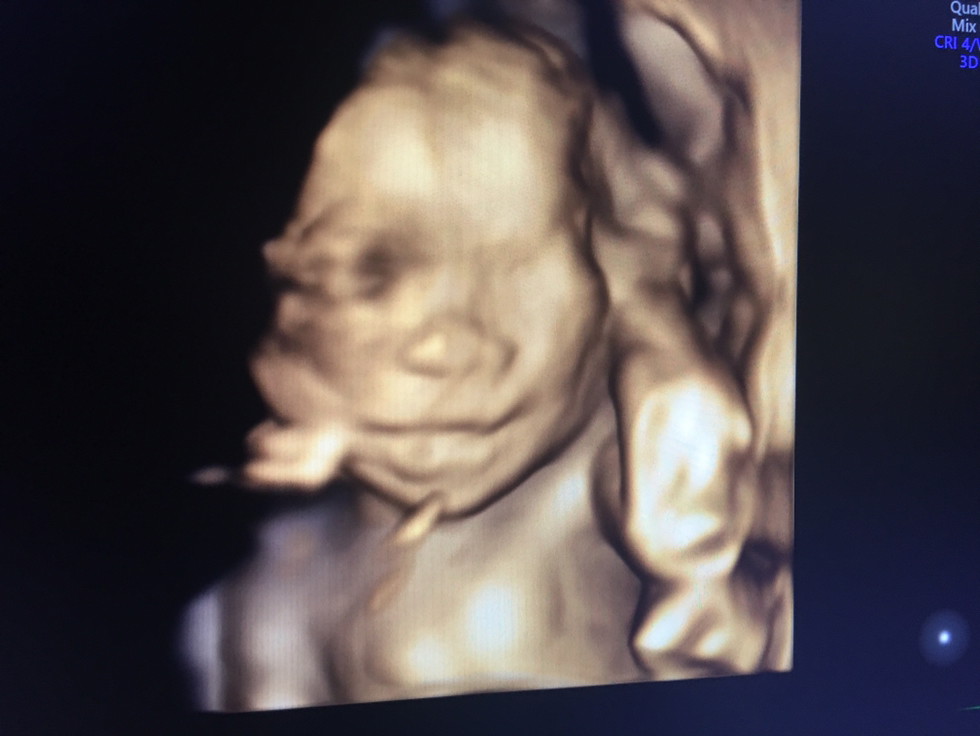

29 weeks!